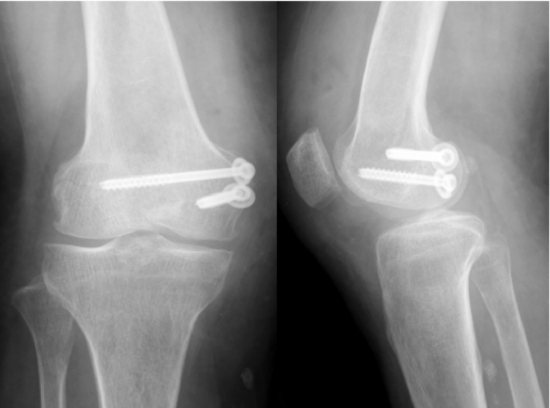

谷文光教授介绍,由于股骨髁形态不规整,内固定物很容易进入髁间窝导致